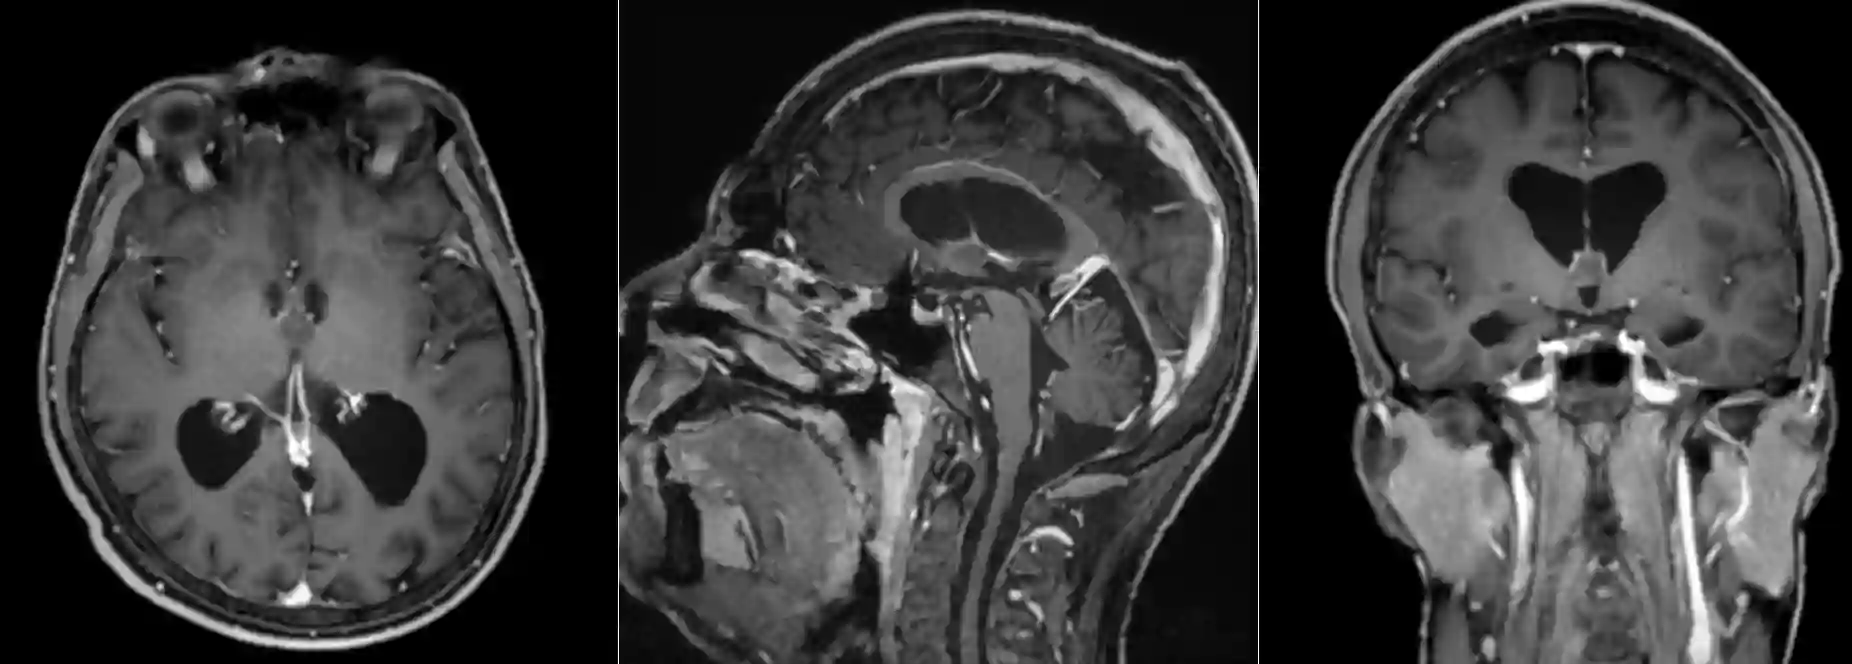

Kolloidzysten können in einer CT oder MRT Bildgebung dargestellt werden, wo sich die Zyste üblicherweise im anterioren Anteil des dritten Ventrikels befindet. In der MRT als auch CT Bildgebung zeigen sich Kolloidzysten variabel jedoch üblicherweise wie folgt[^2]:

MRT Bildgebung

MRT T1 Sequenz | MRT T2 Sequenz | MRT T1 mit Kontrastmittel |

Hyperintense | Hypointense | Minimales Enhancement, teils nur die Kapsel |